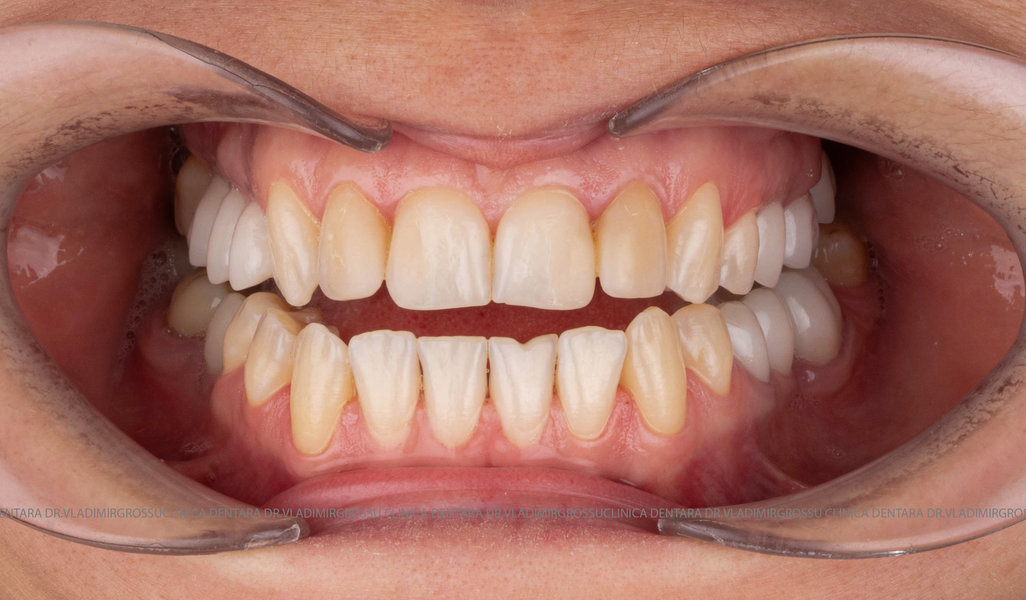

Designul noului zâmbet

În cazul în care pacientul pune la dispoziție fotografii vechi, acestea sunt analizate, însă adesea reabilitarea presupune crearea unui zâmbet nou, personalizat. Pacienții adesea au preferințe clare privind forma și aspectul dinților viitorului zâmbet, iar echipa medicală depune toate eforturile pentru a le respecta dorințele. Dacă este cazul, se propune un design alternativ, explicat pe larg pacientului, care, de regulă, îl acceptă. Protocolul foto-video este indispensabil pentru realizarea unor astfel de lucrări.

Stabilirea lungimii și formei dinților pentru efectul de întinerire

Parametrii estetici ai dinților – lungime, lățime și formă – se adaptează caracteristicilor anatomice individuale ale pacientului. Orizontul zâmbetului corespunde, în general, orizontului pupilelor, iar lungimea dinților este influențată de scheletul maxilarului superior, poziția și mobilitatea buzei superioare. Totuși, frumusețea este subiectivă și personalizată.

Transformările estetice și impactul reabilitării asupra vieții pacienților

Reabilitarea dentară produce o schimbare vizibilă și profundă în aspectul pacientului, cu efecte pozitive evidente asupra stimei de sine și a calității vieții. Mulți pacienți relatează bucuria redobândirii funcției masticatorii și dispariția complexelor legate de aspectul dentar.